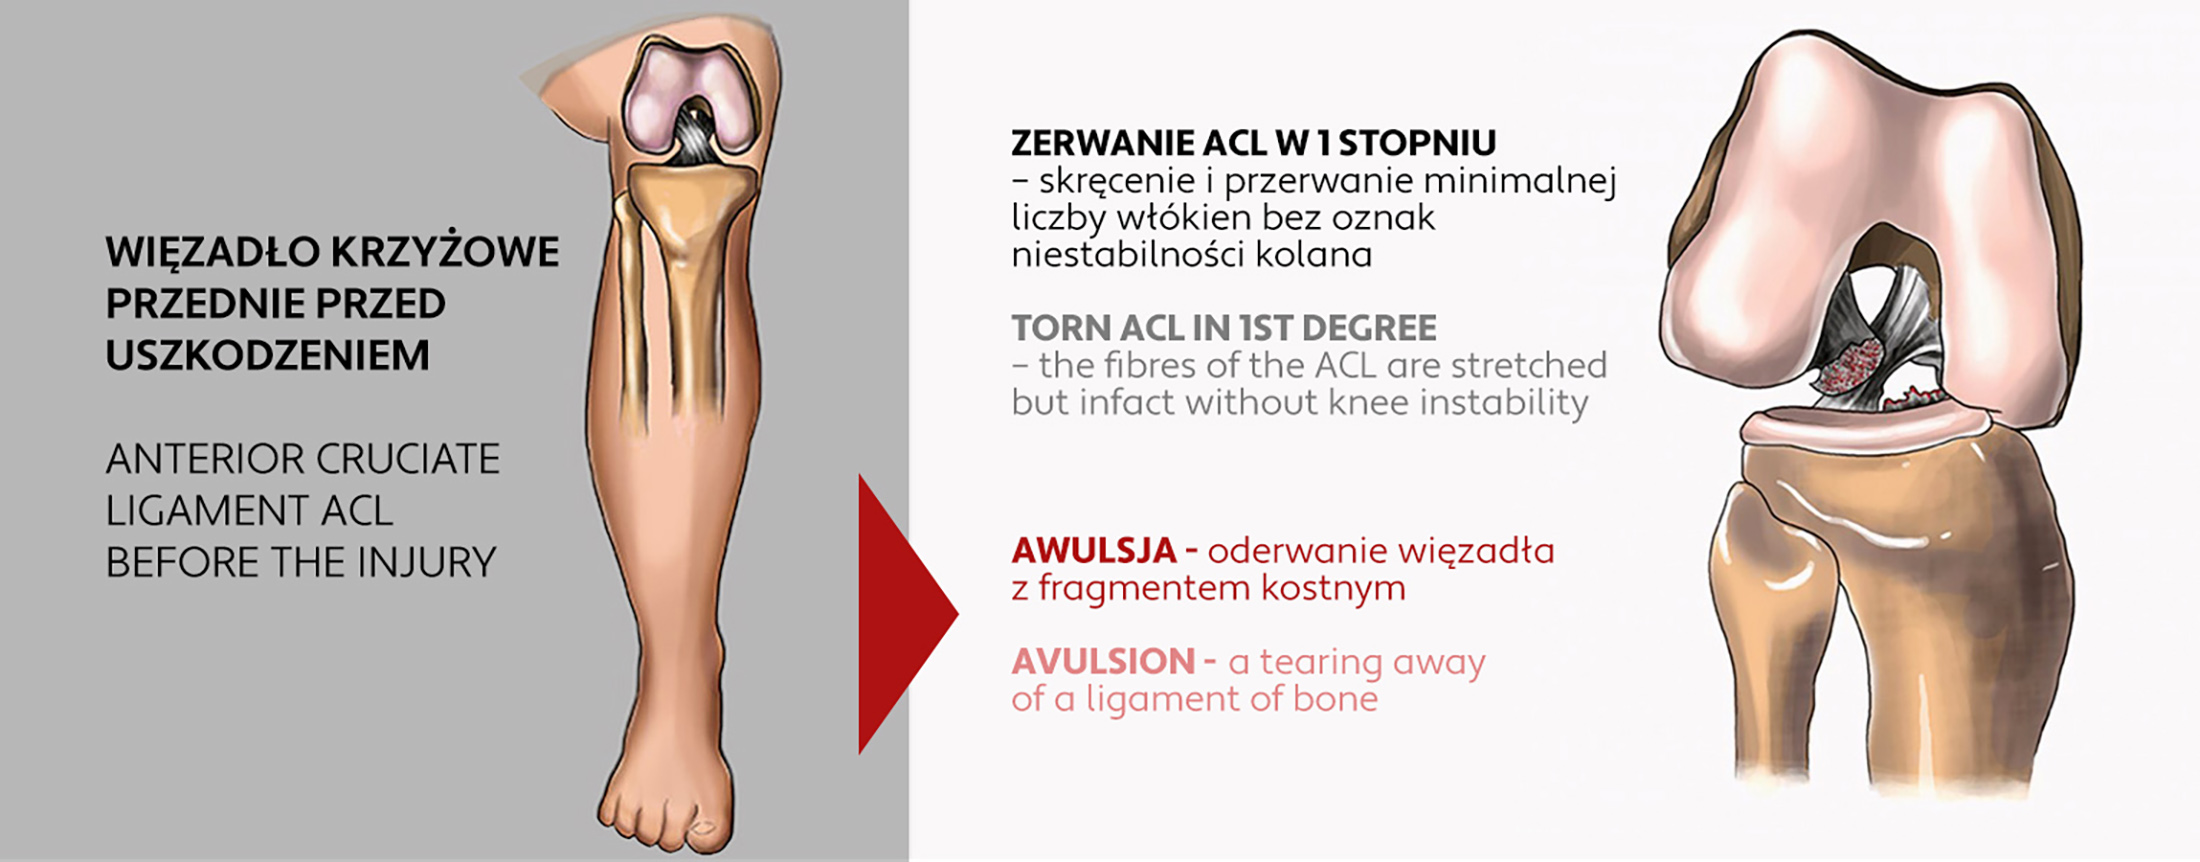

LIGAMENT INJURIES

The ligaments of the knee are short bands of tough, elastic connective tissue that provide stability to the joint. Knee ligament injuries can be caused by impact or injury during physical activity. One of the most common examples is twisting the knee while playing basketball or skiing.

The knee has four large ligaments that connect the bones together to form the joint. They provide stability and strength to the joint. We can observe an injury to the anterior cruciate ligament (ACL), the posterior cruciate ligament (PCL) and the medial collateral ligaments (MCL) and lateral collateral ligaments (LCL). We may have a stand-alone ligament injury or a combined injury where two ligaments are damaged. Ligament injuries range from the least serious, i.e. pulling and tearing, to very serious, i.e. rupture, resulting in complete instability of the joint. Regardless of whether the specialist recommends conservative or surgical treatment, in both cases rehabilitation and immobilization of the joint in a professional knee brace OKD-27, will be necessary.